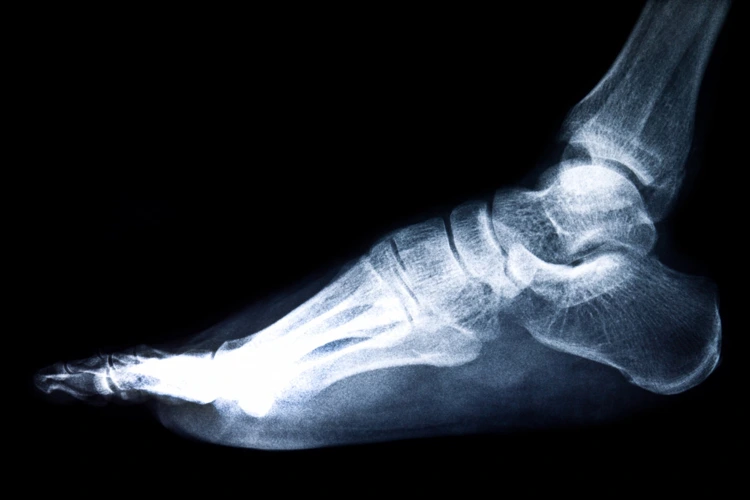

- X-Ray: Radiographs (x-rays) of the foot are helpful to rule out other possible causes of pain like calcaneal stress fractures. It may also show a plantar heel spur, a feature commonly associated with plantar fasciitis. The x-rays also can also show other structural issues like flat feet or high arches.